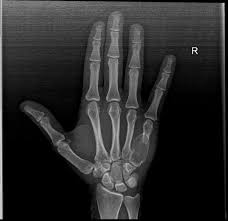

Aneurysmal Bone Cyst Radiology Case Radiopaedia Org Hand Therapy Cysts Radiology